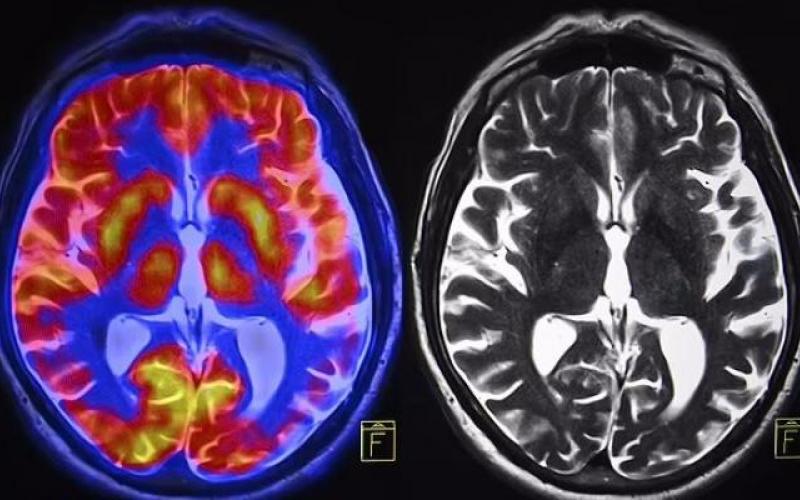

به گزارش سیتنا، دکتر وینود منون، استاد روانپزشکی دانشگاه استنفورد و تیمش، مدلی بر پایه شبکه عصبی عمیق طراحی کردند که می‌تواند با دقت بالای ۹۰ درصد اسکن‌های تصویربرداری تشدید مغناطیسی کارکردی مغز افراد را به دو دسته زن و مرد تفکیک کند.

نتایج نشان داد تفاوت‌هایی در نواحی مغزی مسئول خیال‌پردازی، حافظه و تصمیم‌گیری بین دو جنس وجود دارد.

بیشتر این تفاوت‌ها مربوط به شبکه حالت پیش‌فرض، جسم مخطط و شبکه لیمبیک است که نقش مهمی در فرایندهای ذهنی مانند رویاپردازی، برنامه‌ریزی، تصمیم‌گیری و احساسات دارند.